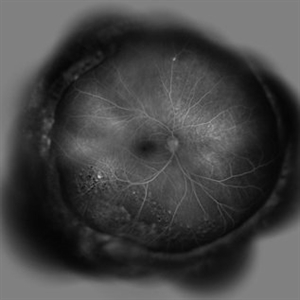

Behcet's Disease Behcet's DiseaseMar 13 2013 by Hamid Ahmadieh, MD Early phase FA of the right eye of a 23-year-old man with retinal vasculitis and branch retinal vein occlusion (BRVO) due to Behcet's disease . Photographer: Solmaz Shahmohammad, Negah Eye Center, Tehran Imaging device: Heidelberg Spectralis Condition/keywords: branch retinal vein occlusion (BRVO), retinal vasculitis

Behcet's Disease Behcet's DiseaseMar 13 2013 by Hamid Ahmadieh, MD Mid phase FA of the right eye of a 23-year-old man with retinal vasculitis and branch retinal vein occlusion (BRVO) due to Behcet's disease . Photographer: Solmaz Shahmohammad, Negah Eye Center, Tehran Imaging device: Heidelberg Spectralis Condition/keywords: branch retinal vein occlusion (BRVO), retinal vasculitis

Behcet's Disease Behcet's DiseaseMar 13 2013 by Hamid Ahmadieh, MD Late phase FA of the right eye of a 23-year-old man with retinal vasculitis and branch retinal vein occlusion (BRVO) due to Behcet's disease . Photographer: Solmaz Shahmohammad, Negah Eye Center, Tehran Imaging device: Heidelberg Spectralis Condition/keywords: branch retinal vein occlusion (BRVO), retinal vasculitis

Behcet's Disease Behcet's DiseaseMar 13 2013 by Hamid Ahmadieh, MD Wide field FA of the right eye of a 23-year-old man with retinal vasculitis and branch retinal vein occlusion (BRVO) due to Behcet's disease . Photographer: Solmaz Shahmohammad, Negah Eye Center, Tehran Imaging device: Heidelberg Spectralis Condition/keywords: branch retinal vein occlusion (BRVO), retinal vasculitis